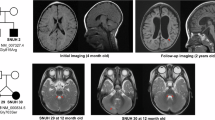

WDR4 is one of the genes whose mutations are implicated in cerebellar developmental disorders. It encodes a protein with seven WD40 structural motif repeats, and its mRNA is expressed in various tissues, including the kidney, thymus, liver, stomach, lung, testis, and brain [7]. A variety of WDR4 mutations, including homozygous missense mutations, homozygous splice site mutations, and compound heterozygous mutations have all been identified in patients with neurodevelopmental disorders, including primordial dwarfism [8,9,10] and Galloway-Mowat syndrome [11]. These patients exhibit neurodevelopmental defects, accompanied with growth retardation, cerebellar atrophy, motor development delay, and gait dysfunction phenotypes. Interestingly, parents of patients carrying a single wild type (WT) WDR4 allele do not present any phenotype, indicating the recessive nature of this disease-associated allele. Although clinical findings imply a role of WDR4 in brain development, it has not been experimentally validated yet. Even more so, the molecular mechanisms underlying these neurodevelopmental phenotypes are completely unexplored.

Developmental disorders affect 2–5% of individuals worldwide [44, 45]. However, their heterogeneous causes and varying phenotypes make it difficult to analyze the underlying mechanisms, thus limiting treatment options. Recently, whole-exome sequencing (WES) technology has made progress in linking genetic variants to clinical phenotypes. Through WES, various WDR4 mutations were identified in patients with neurodevelopmental disorders [8,9,10,11]. In addition to growth retardation, global developmental delay, microcephaly, and intellectual disability, the phenotypes of cerebellar atrophy and motor development delay are shared in some of these patients. Importantly, these phenotypes are recapitulated in our Wdr4 mouse model where Wdr4 is conditionally deleted in cerebellar GNPs. The consistent phenotypes between the WDR4-mutated patients and the Wdr4-deficient mouse model suggest a cause-effect relationship, more than an association. In addition, while patients with either homozygous variants, or compound heterozygous variants have neurodevelopmental defects, their parents who carry one WT WDR4 allele did not display these phenotypes, suggesting that one allele of WT WDR4 is sufficient to maintain proper function. Importantly, this phenomenon is also recapitulated in the Wdr4 conditional deletion mouse model. Thus, our mouse model is suitable for studying the underlying mechanisms of cerebellar atrophy caused by Wdr4 variants and for testing potential therapeutic strategies for these patients.